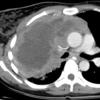

Lymphoma CT

Date: 04/25/2009

Views: 2890